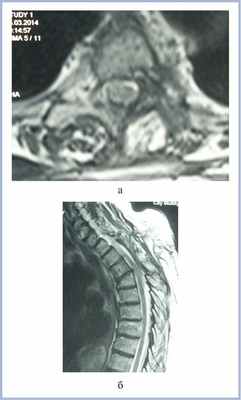

Пациентка В., 66 лет, поступила в клинику с жалобами на боли в межлопаточной области, усиливающиеся при физической нагрузке. Интенсивность боли оценивала в 6—7 баллов по визуально-аналоговой шкале (ВАШ). Боль в межлопаточной области беспокоит в течение 14 лет. При МРТ выявлено экстрамедуллярное объемное образование на уровне Th3—Th4 позвонков слева, с экстра- и интрадуральным компонентом, распространяющееся в межпозвонковое отверстие Th3—Th4 (рис. 1).

Рис. 1. МР-томограммы (Т1-ВИ с контрастным усилением) пациентки с менингиомой на уровне Th3—Th4 позвонков перед операцией в аксиальной (а) и фронтальной (б) проекциях. Определяется объемное образование (менингиома) на уровне Th3—Th4 позвонков, распространяющееся в межпозвонковое отверстие.

На следующий после выписки день пациентка отметила появление припухлости в области послеоперационного рубца, онемение и слабость в ногах, что послужило причиной для повторной госпитализации в стационар. В неврологическом статусе при поступлении доминирует синдром заднестолбовой атаксии (снижение вибрационной чувствительности с уровня Th5—Th6 позвонков, неустойчивость в позе Ромберга), оценка по шкале Klekamp—Samii 18 баллов. При МРТ верифицирована ликворная киста (псевдоменингоцеле) в зоне оперативного вмешательства, дислоцирующая спинной мозг кпереди (рис. 2).

Рис. 2. МР-томограммы пациентки (Т2-ВИ) с менингиомой на уровне Th3—Th4 позвонков перед второй операцией в аксиальной (а) и сагиттальной (б) проекциях. Определяется компрессия спинного мозга жировым лоскутом и ликворной кистой больших размеров.